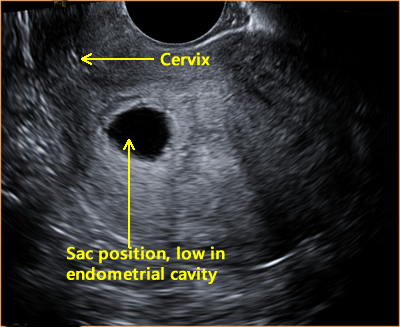

The gestational sac forms early in pregnancy to enclose an embryo and amniotic fluid. Certain sac characteristics can indicate a compromised pregnancy.

Predicting pregnancy failure in 'empty' gestational sacs - Nyberg - 2003 - Ultrasound in Obstetrics & Gynecology - Wiley Online Library

Defining safe criteria to diagnose miscarriage: prospective observational multicentre study

First-Trimester Ultrasound: Early Pregnancy Failure - First-Trimester Ultrasound: A Comprehensive Guide

Early Pregnancy Loss (Embryonic Demise) Imaging: Practice Essentials, Ultrasonography

Early pregnancy ultrasound explained : GS , YS and FP